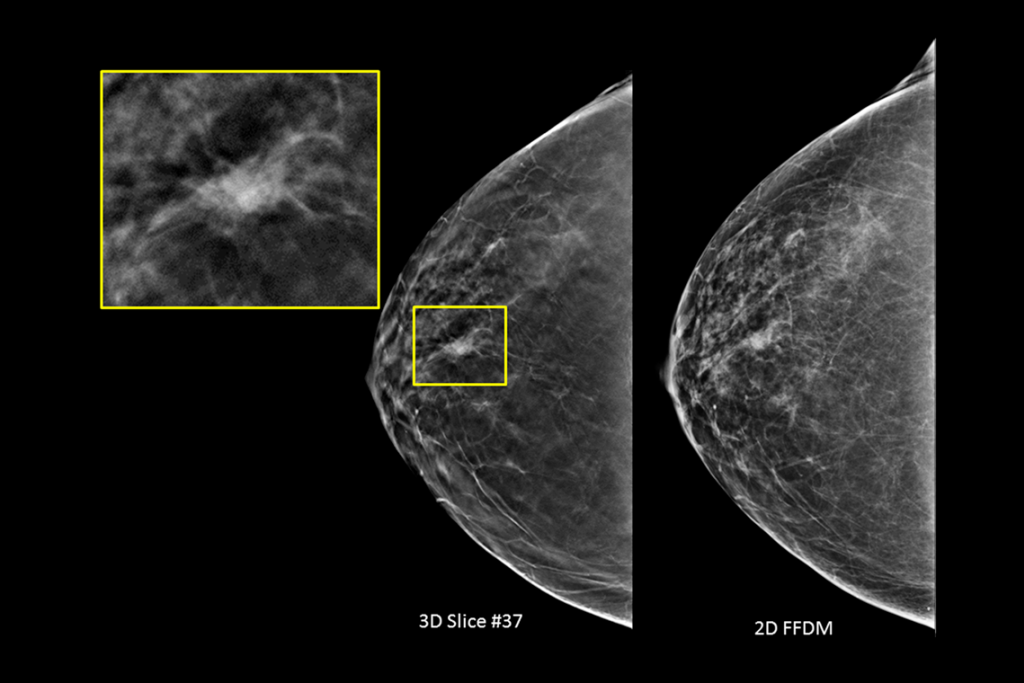

Klinische Aufnahmen einer Brustuntersuchung mit verdächtiger Läsion